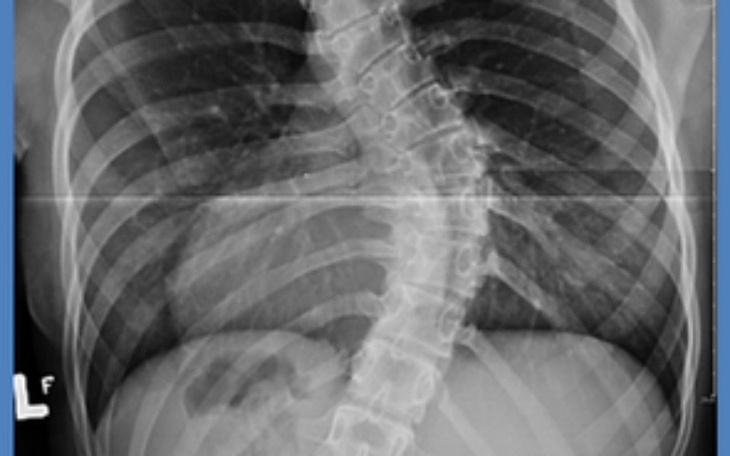

Dzień dobry potrzebuje pieniędzy na leczenie. Mieszkam sama nie mam bliższej rodziny potrzebuje bardzo szybko pieniędzy na gorset .